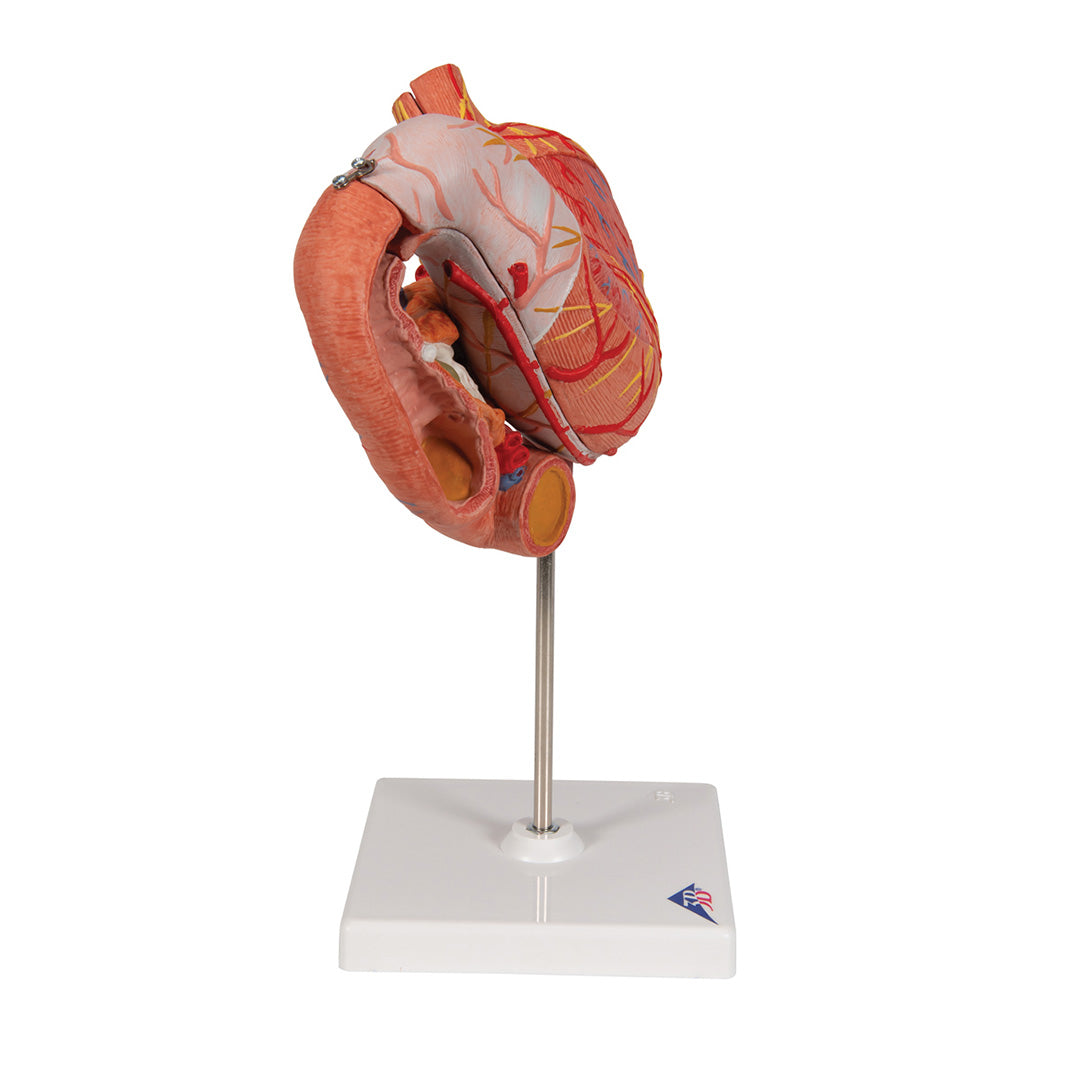

Estómago, en 3 piezas

Estómago, en 3 piezas

El modelo presenta las capas de la pared del estómago desde la cardia hasta el píloro.

La mitad delantera del estómago se puede retirar.

Se presentan:

• Parte inferior del esófago

• Conductos

• Nervios

• Duodeno

• Páncreas

Con soporte.

Peso 0.87 kg.

Dimension 25 x 22 x 12 cm